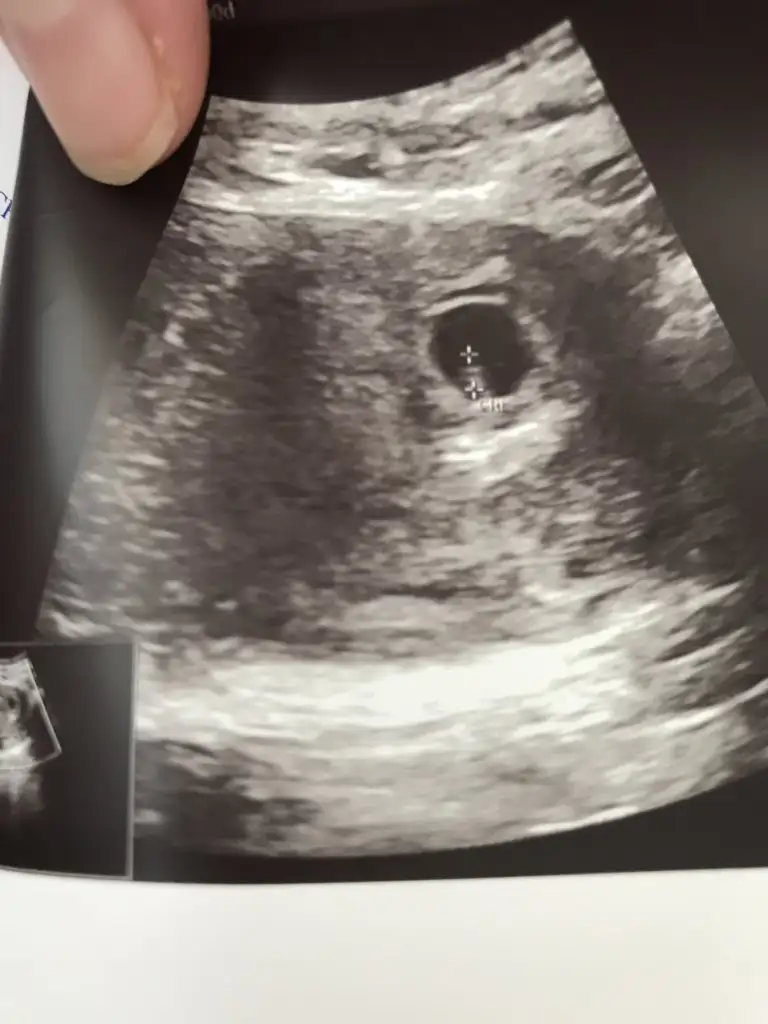

Buda benim minnoş 5 hafta 5 günlükken vajinal ultrason görüntüsü kalp atışını duyamadım ama gördük çok şükür

Benim kesede elips şeklinde deneyimli hanımlar sizce

kız mı erkekmi acep :)

3 kiz anasi oldugunuz icin tecrubelerinizden faydanmak isterim. Su an 7+3 uz. Ilk fotoya gore kiz demistiniz. Benim icime doganda oyle. Peki sizin keseniz de boyle fasulye gibi miydi sizce kese sekli onemli mi?